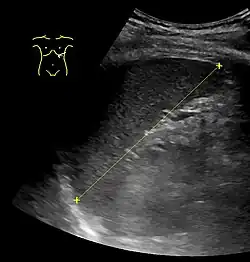

The spleen, in healthy adult humans, is approximately 7 to 14 centimetres (3 to 5+1⁄2 in) in length. It weighs between 1 oz (28 g) and 8 oz (230 g) (standard reference range),[12] correlating mainly to height, body weight and degree of acute congestion but not to sex or age.[13]

Spleen seen on abdominal ultrasonography -

Maximum length of spleen on abdominal ultrasonography -